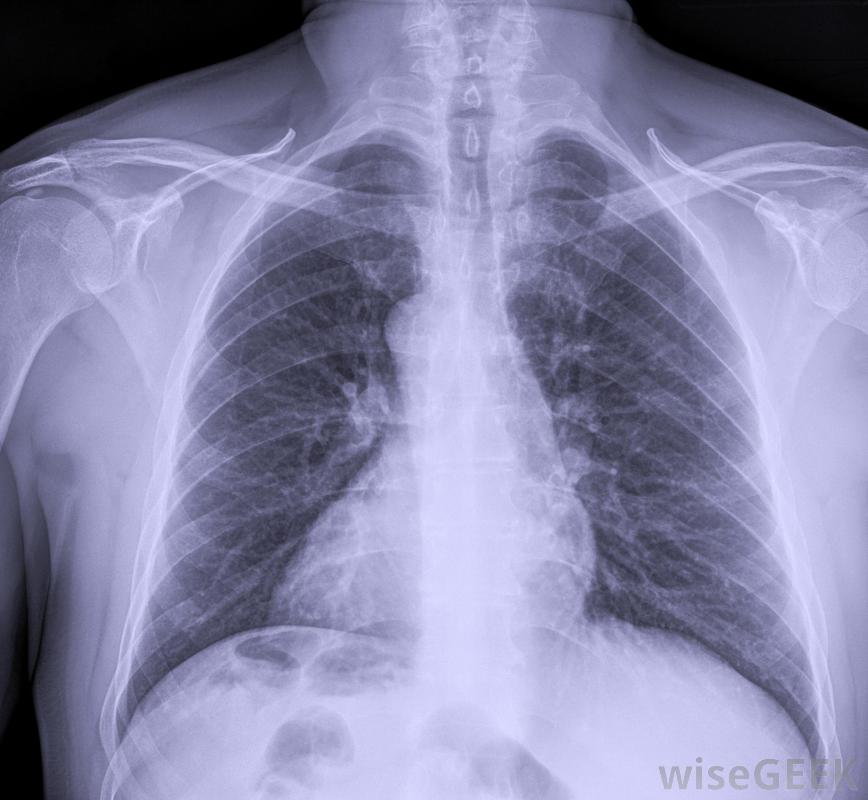

在使用前,将进行胸部X光检查,以确保PICC管路已正确放置。这些类型的静脉输液管可由受过专门培训的护士、放射科医生或医生插入助手。这项手术通常在无菌条件下在床边进行。超声检查上臂发现的大静脉。在PICC线就位后,在使用该线之前,要进行胸部x光检查以确认放置是否正确PICC线既可以用来给药,也可以用来抽血。病人需要PICC的原因有很多一些病人可能需要长期化疗或抗生素。这些外周插入的中心导管可以在原位放置数月,这使它们成为长期使用的理想选择

超声波机用于显示PICC线路上臂部的大静脉一旦对PICC线的需求结束,就可以很容易地将其拆除。这可以由护士或其他经过适当培训的医护人员来完成。一旦拆除了PICC线,就要测量其长度,以便与插入长度进行比较。这将确认所有的线路都被拆除了